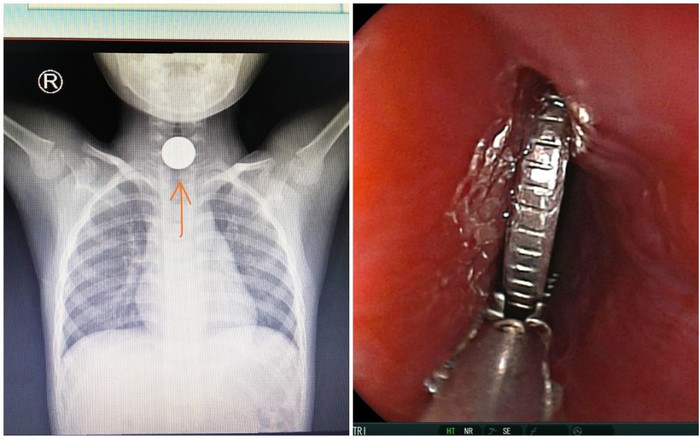

Các bác sĩ Bệnh viện Nhi đồng TP HCM đã thực hiện cấp cứu thành công bé trai 5 tuổi bị dị vật là đồng xu mắc trong cổ họng ngày mùng 1 Tết.

Thông tin từ BV Nhi đồng 1 TP HCM cho biết, bé ngậm đồng xu khi chạy chơi với các bạn cùng nơi ở. Trong lúc nô đùa đã vấp ngã, nuốt luôn đồng xu và đồng xu kẹt lại cổ họng, thành dị vật gây tắc đường thở. Sau đó, cháu được đưa đến Bệnh viện Nhi đồng thành phố cấp cứu trong tình trạng khó thở, ho sặc sụa.

Hình ảnh chụp X-quang cho thấy dị vật bị mắc trong cổ họng. (Ảnh: BV Nhi đồng TP HCM).

Ngay sau đó, các bác sĩ nhanh chóng tổ chức nội soi, gắp dị vật kịp thời, cấp cứu thành công cháu bé.

Bác sĩ chuyên khoa I Lê Đức Lộc, Trưởng kíp cấp cứu cho biết đồng xu mắc kẹt ngay tại ngã ba hầu họng và đường thở. Nếu không được cấp cứu kịp thời, bệnh nhi sẽ bị khó thở, nhiễm trùng với nhiều hệ lụy khó lường.

Hình ảnh nội soi dị vật. (Ảnh: BV Nhi đồng TP HCM).